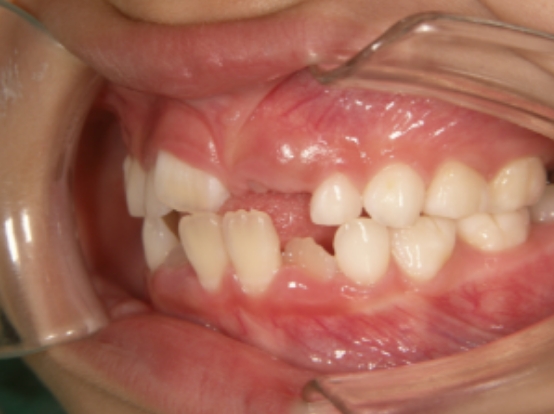

治療中③ 小2:7y11m QH・BHで側方拡大、前歯の並べ替え